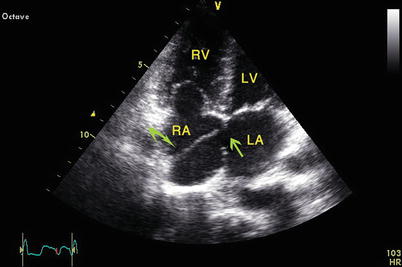

The video demonstrates an transesophegeal echo (tee) of a moderate to large secundum asd and right heart enlargement, first showing basic anatomical description, then. The most frequent congenital heart lesion initially diagnosed as an. Atrial septal defect (asd) is the second most common congenital heart defect after ventricular septal defects and the most common to become symptomatic in adulthood.

Classification • primum asd • secundum asd • sinus venosus defects • coronary sinus defects • (patent foramen ovale).

Unroofed coronary sinus (ucs) is a rare cardiac anomaly that results in communication between the coronary sinus and the left atrium. Many children have no symptoms and seem healthy. When blood passes through the asd from the left atrium to the right atrium, a larger volume of blood than normal must be handled by the right side of the heart. Optimal visualization of a coronary sinus asd requires selective left svc, right upper pulmonary vein, or left atrium contrast injection in the hepatoclavicular view.